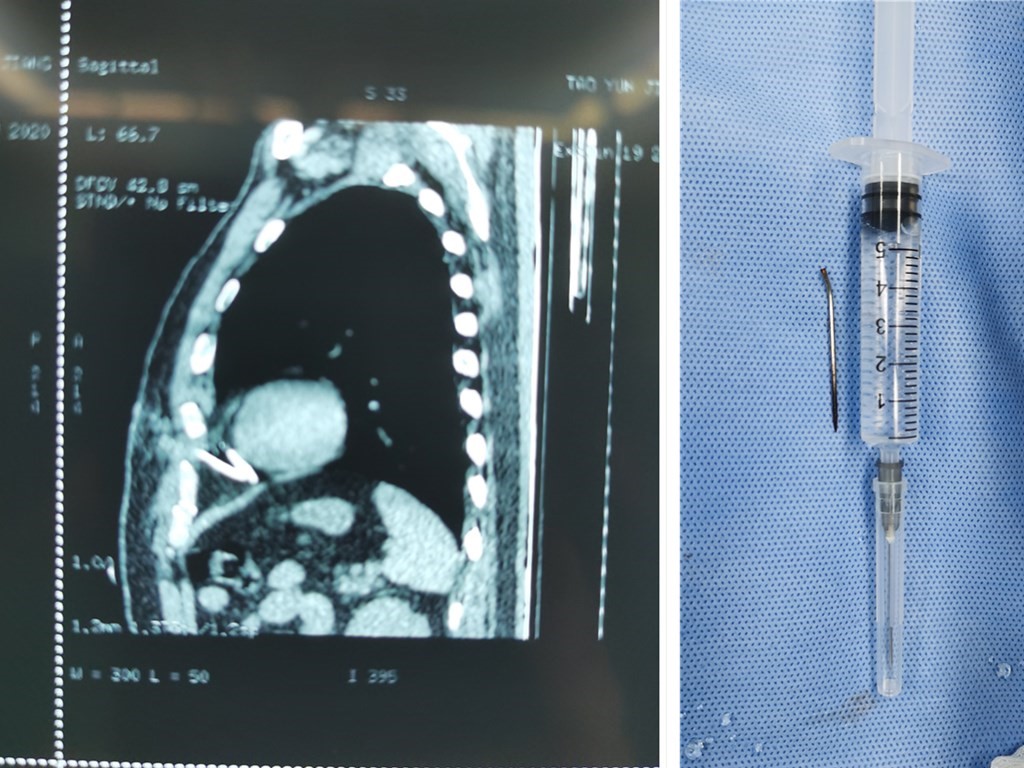

6月19日,一名大汗淋漓的患者来我院急诊科就诊,接诊时,患者左侧胸部剧烈疼痛,伴有呼吸困难,接诊医生详细询问病情及查体,了解到该患者于1天前不慎将一枚长约5cm的粗针自左侧前胸壁完全刺入胸腔内,进行相关检查提示左侧胸腔内金属异物,异物位于心包腔。患者病情危重,尖锐的金属异物随时可能刺破心脏及大血管,造成心脏破裂及大出血,导致死亡。

时间紧迫,我院胸心外科杨景春主任紧急会诊后决定立即手术取出异物。与患者家属交代相关手术风险,征得患者家属同意后立即送入手术室行胸腔镜下“左侧胸腔探查术”。打开心包显露心肌,最终于左心室与右心室间隙内发现一枚长约5cm的“钢针”,并将其完整取出,整个手术过程历时了1个多小时,术中未对心脏、肺组织、血管等造成损伤,出血不足10ml。术后,患者左侧胸部疼痛完全缓解,很快便痊愈出院。